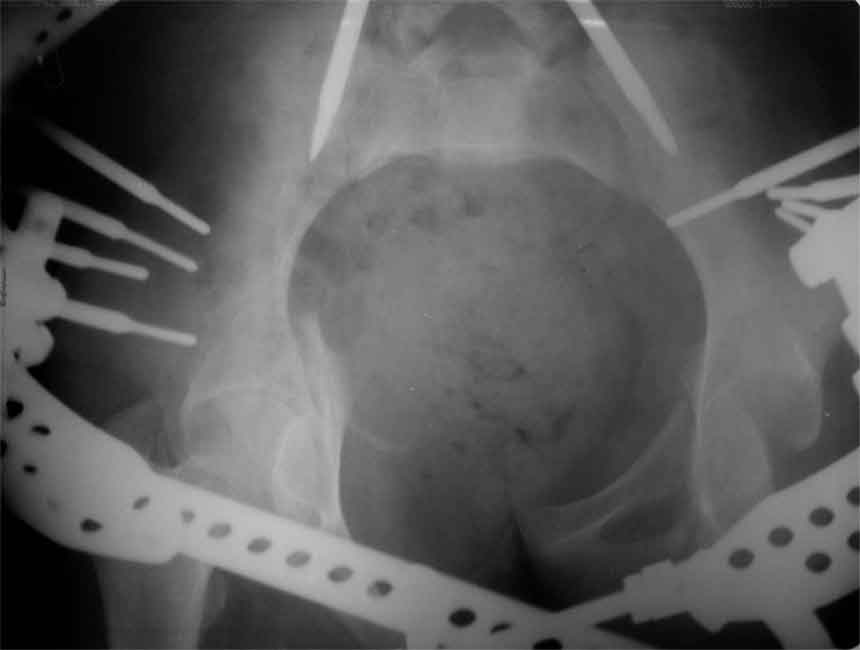

продолжение темы. не увидел энтузиазма в обсуждении. Вопросы прежние, первым этапом закрыто устранили вертикальное и передне-заднее смещение. Каким образом восстановить целостность тазового кольца, из каких доступов? Снимки в приложении

передне-неружным внебрюшинным доступом к лонно-седалищномц сочленению - синтез штангами(можно из заднего доступа, но хуже обзор и труднее репозиция), из этого же доступа к крыше вертлужной впадины - синтез реконструктивными пластинами(мы делали "ChM" тазовыми, хорошо себя зарекомендовали), передним доступом на лонное сочленение - синтез подобной пластиной. к задней колонне вертлужной впадины - задне-наружный доступ, синтез такой же пластиной. КРОВОПОТЕРЯ!!! возможно до 7л. мощная ангтибак. профилактика во время и после операции. до перехода на заднюю колонну оперировать в аппарате. бвл подобный случай, по снятии аппарата через 8 мес. - рецедив смещений сразу.